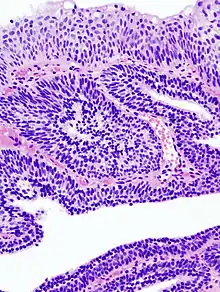

Le papillome est une petite tumeur bénigne constituée d'axes conjonctifs bordés par des cellules épithéliales.